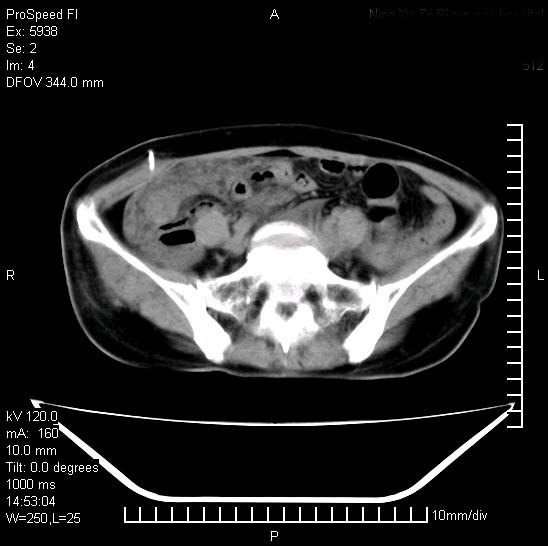

反复小腹疼痛,盆腔积液3年,无发热,曾抗痨一段时间。

右下腹肠管壁增厚,边缘有侵润改变及点状低密度影,内侧可见局限性肿块。考虑-----淋巴瘤或增生型肠结核----盆腔积液-----建议肠镜检查

考虑盆腔及右下腹感染性病变(结核可能)。

结核性腹膜炎伴积液。右侧髂骨骨窗看看,是否有骨质破坏。

提示结核性腹膜炎合并盆腔积液。建议查ppd或tb抗体。

考虑右下腹及盆腔感染性病变(结核?)。